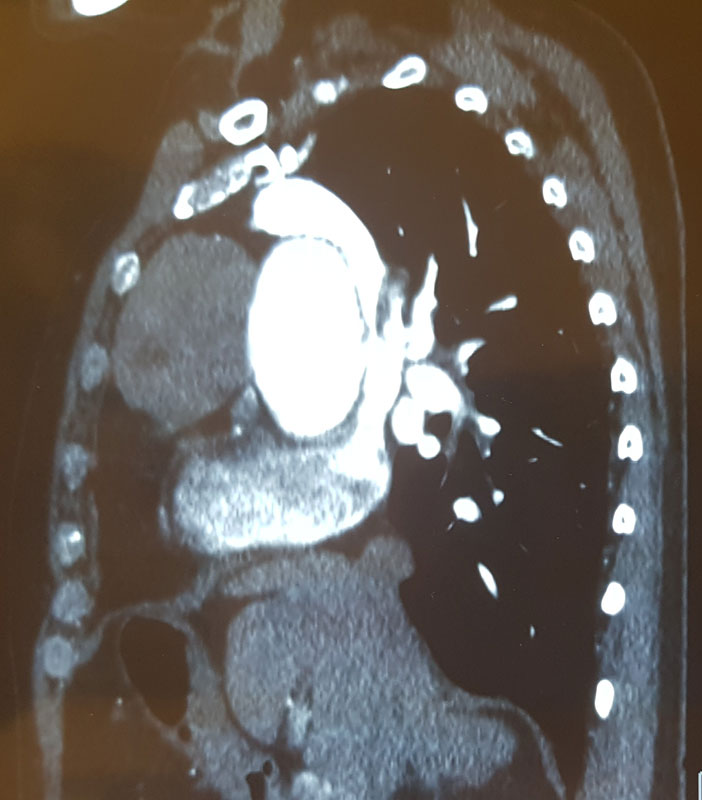

В Клинике грудной и сердечно-сосудистой хирургии им. Святого Георгия начато выполнение операций аортокоронарного шунтирования с применением методики ЮрЛеон и с использованием Левосимендана у больных ИБС со сниженной фракцией выброса.

Впервые в России имплантирован венозный стент нового поколения VENOVO, выполнена реканализация и стентирование глубоких подвздошных вен у пациента с синдромом нижней полой вены, развившегося после билатерального илио-феморального тромбоза

В Пироговском Центре проведена уникальная успешная операция по удалению опухоли правого предсердия с остановкой сердца на 3 минуты без подключения к аппарату искусственного кровообращения

В Пироговском Центре проведена уникальная успешная кардиохирургическая операция на открытом сердце без подключения к аппарату искусственного кровообращения

Первая робот-ассистированная операция на сердце — аортокоронарное шунтирование

Первая робот-ассистированная операция аорто-бедренного шунтирования